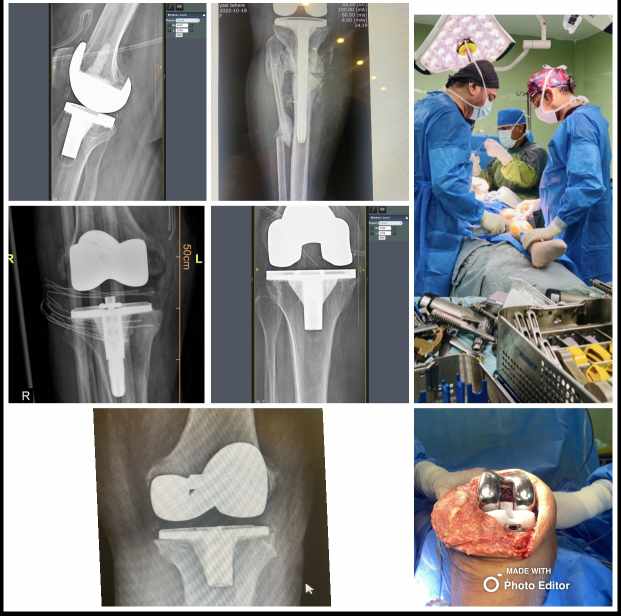

تعویض مفصل زانو و لگن،درمان زانوی پرانتزی،ضربدری،درمان انواع شکستگی لگن،استابولوم،ارتروسکوپی مچ پا ،زانو،شانه،درمان انواع شکستگی های اندام ها،بازسازی رباط های صلیبی،

نمونه کارها